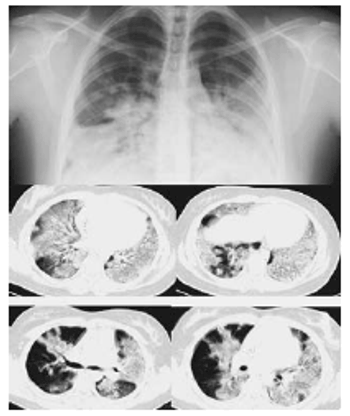

Findings of a Canadian study suggest CT might be better than the standard chest x-ray to show the extent and characterization of H1N1 flu.